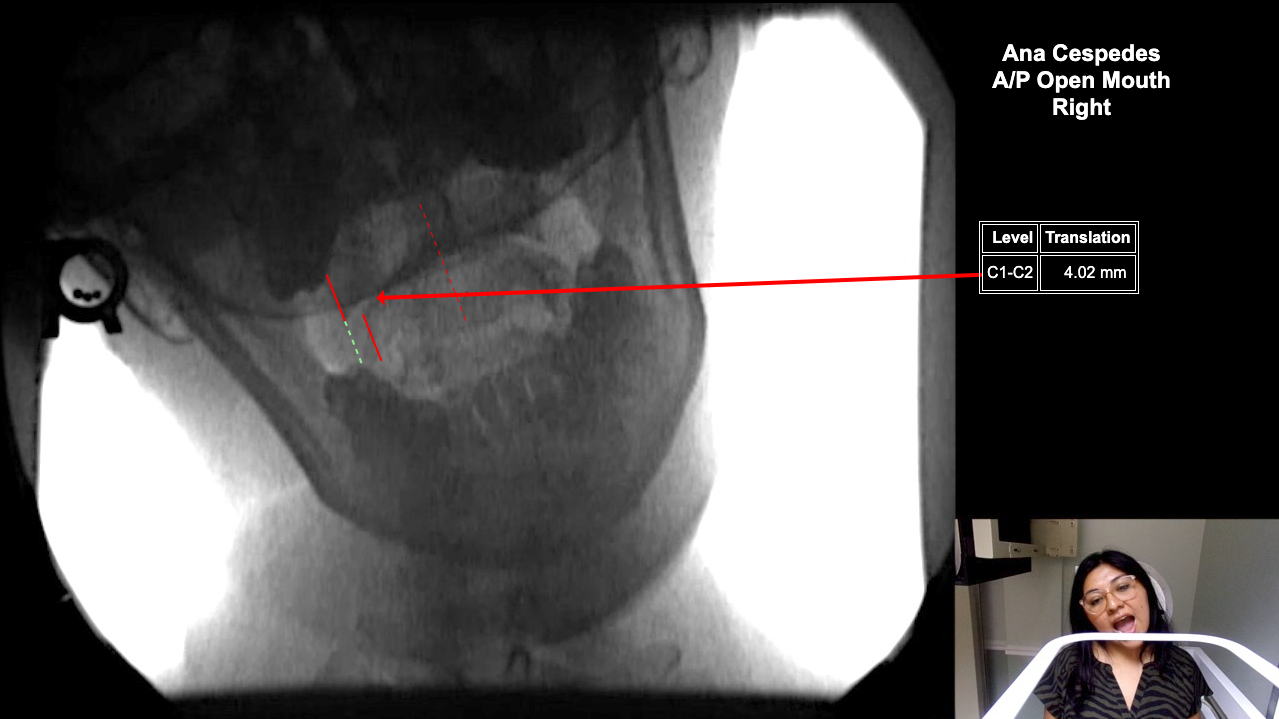

Home > Ana Cespedes